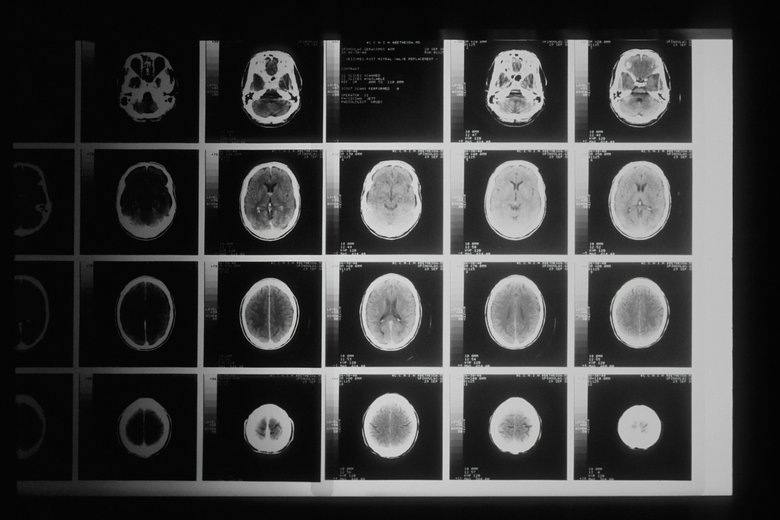

Рак мозга использует сахар для роста, выяснили ученые